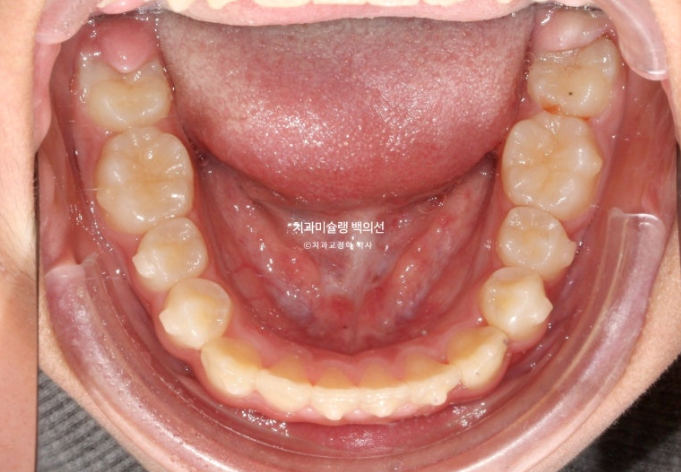

공간부족으로 인한 덧니가 심해 반대교합이 있습니다.

악궁확장을 통한 덧니배열을 목표로 인비절라인퍼스트 교정치료 권유드렸습니다.